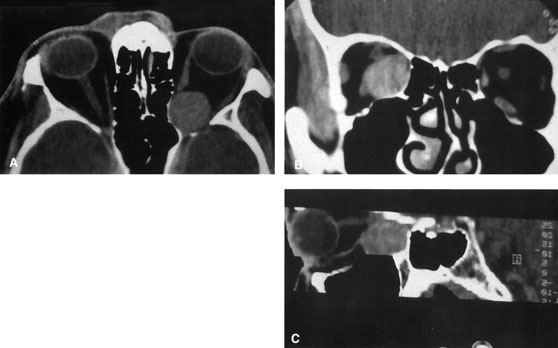

Magnetic resonance imaging is useful in selected cases, especially when evaluating the orbital cranial junction. Significant bony artifact and a lack of orbital fat in the orbital apex make CT scan resolution of the orbital apex structures poor. Because cortical bone has low signal on MRI, there is no bone artifact when viewing the orbital apex on MRI. The lack of intervening fat in the apex to provide contrast is overcome on MRI because contrast is provided by the individual nuclear characteristics of each tissue so that the orbital apex structures are visualized well. Consequently, conditions that affect the optic nerve and chiasm, such as optic nerve meningioma and glioma, generally are evaluated with MRI rather than CT scan (Fig. 2).

Fig. 2. A. Axial orbital CT scan of right optic nerve meningioma. Note lack of detail in orbital apex. B. Axial orbital MR image, same patient. Note increased detail in orbital apex owing to lack of bone artifact. C. MRI with gadolinium contrast. Note extension into brain not easily appreciated with CT scanning or MRI without contrast.